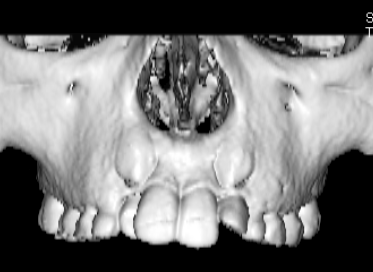

治療法:上顎急速拡大装置+クリアスナップ+フェイスマスク+上顎3番は開窓牽引CT写真にて位置確認

FX(フェイシャルアキシス)は85度なので東洋人の平均値に近く、下顎が前方に過剰成長するリスクは強くはありません。

しかしやはり上顎は劣成長で、下顎が優位な状態ではあります。

上下顎のギャップはありますが、顔面自体の幅径は良好な値を示していますので、スペース不足は拡大することによって解決できポテンシャルはあると考えられます。

左右の非対称もさほど強くありません。